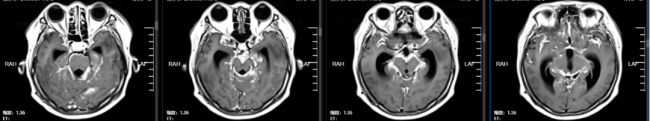

2024年5月18日,患者出现神经系统相关症状,颅脑MR检查提示脑脊髓膜转移。2024年10月29日,患者首次就诊于陶荣杰主任团队的神经肿瘤科。团队结合患者病史、病理特征及脑膜转移的临床特点,制定了全身与局部相整合的治疗方案:采用塞替派全身化疗联合塞替派鞘内注射,以针对性降低脑膜转移的局部肿瘤负荷;同时联用贝伐单抗进行抗血管生成治疗,改善肿瘤微环境并增加血脑屏障通透性;此外,基于患者HR阳性的分子特征,加用达尔西利联合氟维司群(CDK4/6抑制剂联合内分泌靶向治疗),以实现全身肿瘤的综合控制。

2025年3月31日,患者第四次入院,复查颅脑MR提示:脑内、软脑膜、延髓可见多发异常强化,提示多发转移瘤。根据病情变化,团队优化治疗方案,调整为塞替派联合德曲妥珠单抗治疗,以进一步强化靶向治疗效果。2025年6月10日,颅脑MR检查提示病情达到部分缓解(PR),脑膜转移灶较前明显改善,患者临床症状显著缓解。德曲妥珠单抗是一种HER2靶向抗体与DNA拓扑异构酶I抑制剂偶联物,用于治疗HER2表达的实体瘤,包括乳腺癌、胃癌、结直肠癌和非小细胞肺癌。